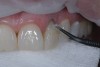

Impressions were taken and a model was made. While the patient performed at-home bleaching, an enhanced wax-up was created. The next appointment involved obtaining patient approval of the enhanced wax-up and performing a shade mock-up. As instructed, the patient discontinued bleaching 2 weeks prior in order to allow rehydration before composite layering. After bleaching, the tooth shade was determined to be between A1 and OM1 (Figure 2).

Fig 2. At-home vital tooth whitening enhanced the shade of the patient’s teeth to between A1 and OM1.

Figure 2